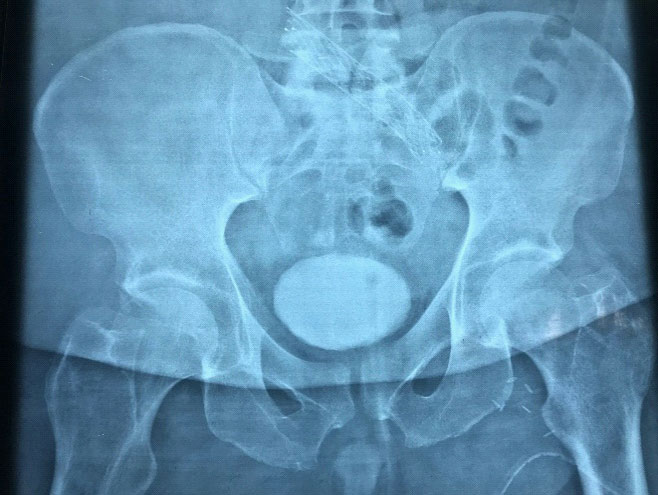

The patient underwent a left venogram and left external iliac vein stenting. Intraoperative findings showed narrowing of the left external iliac vein, which confirm the diagnosis of MTS. A stent measuring 16 mm X 100 mm was deployed in iliocaval junction with a good flow through the stent into IVC (Figure C). Post-surgery, he was started on heparin infusion and was overlapped with oral warfarin. For his venous ulcer, he was put on a vacuum dressing for 2 cycles and then was changed to four-layer compression dressing.

Figure C:Left iliac vein stenting.